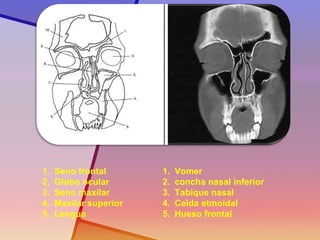

1.Seno frontal

2.Globo ocular

3.Seno maxilar

4.Maxilar superior

5.Lengua

1.Vomer

2.concha nasal inferior

3.Tabique nasal

4.Celda etmoidal

5.Hueso frontal

1.Seno frontal 2.Globoocular 3.Seno maxilar 4.Maxilar superior 5.Lengua 1.Vomer 2.concha nasal inferior 3.Tabique nasal 4.Celda etmoidal 5.Hueso frontal